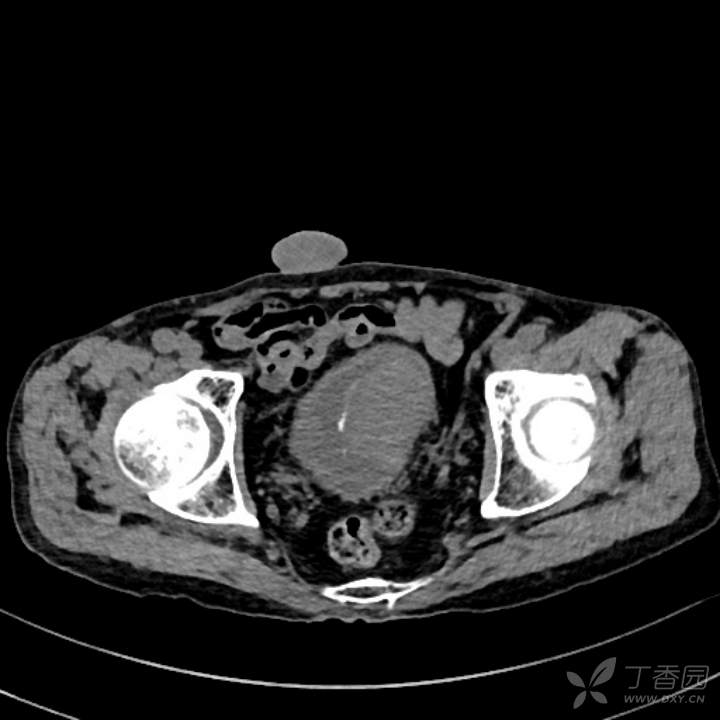

CT:

膀胱左侧壁及三角区见凸向腔内的菜花软组织块,宽基底。